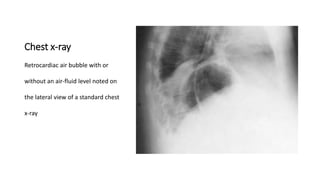

Chest x-ray

Retrocardiac air bubble with or

without an air-fluid level noted on

the lateral view of a standard chest

x-ray